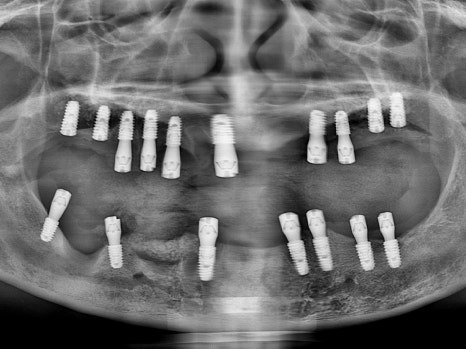

치료 전 파노라마

수술 당일

수면마취로 17개의 임플란트를 식립하였고,